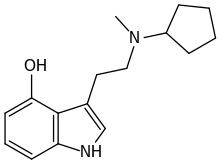

| 4-HO-McPeT | artificial | 4-OH | C5H9 | CH3 | 4-hydroxy-N-cyclopentyl-N-methyltryptamine | 77872-48-1 |